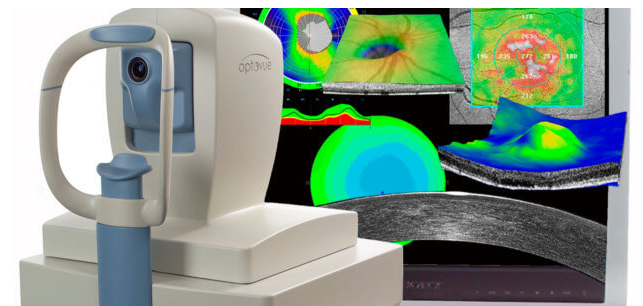

Диагностика зрения: Когерентная томография сетчатки